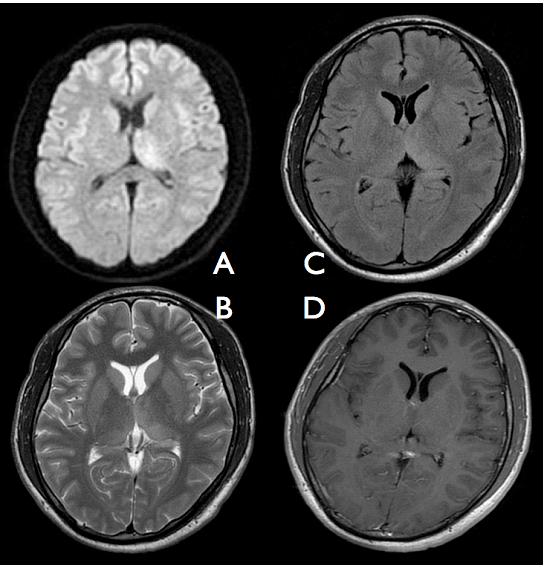

Figure 1